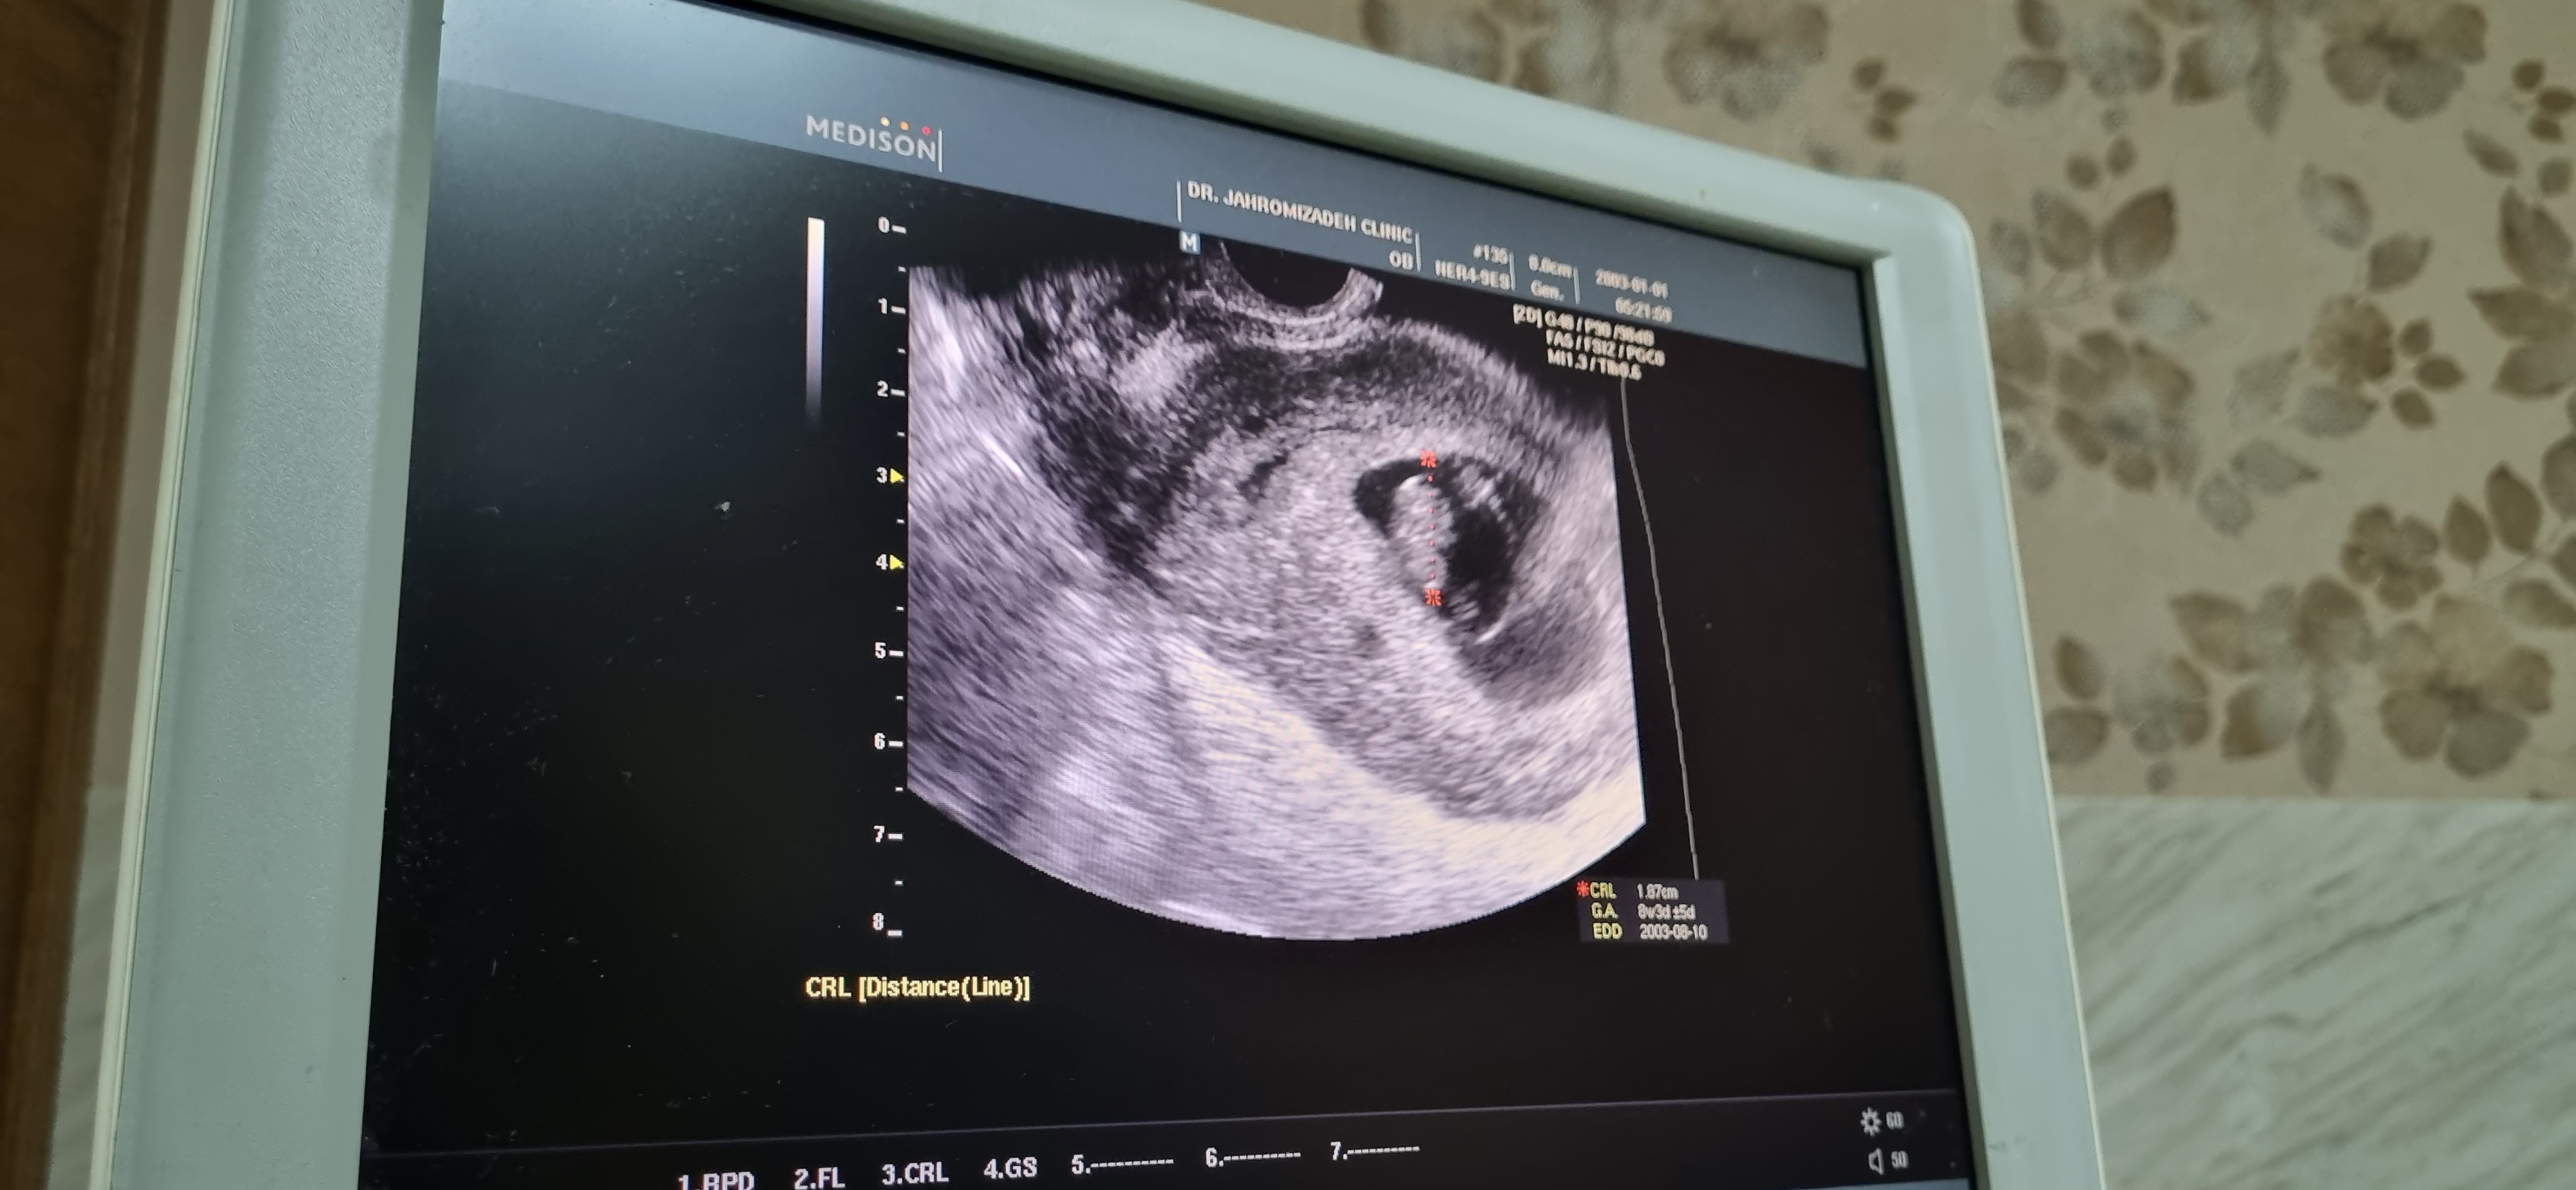

اميد_بر_خدا عضویت: 1398/09/24 تعداد پست: 145 مال منم سمت چپ بود پسرم ببین اگه جنین مثل لوبیا باشه میگن پسره اما اگه شبیه یه توده گوشت دختره دلیل ... ارغوان جون ميشه براي منم حدس بزني نه هفتست

ارغوان30 عضویت: 1395/03/07 تعداد پست: 4657 ارغوان جون ميشه براي منم حدس بزني نه هفتست لوبیا کوچولو بنظرم پسره مبارک باشه انشالله سالم باشه😍 من اونقدر به داشته هام فکر میکنم که وقت نمیشه به نداشته هام فکر کنم❤❤❤